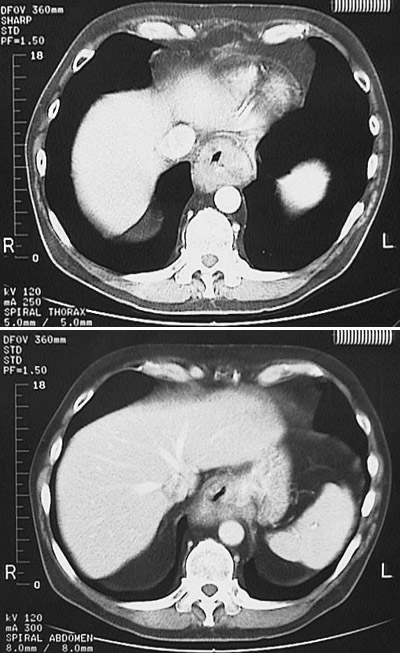

![]() | These abdominal CT scan views with contrast shown above demonstrate a lower esophageal adenocarcinoma extending to the upper stomach. This proved to be an adenocarcinoma arising in a Barrett mucosa that resulted from chronic gastroesophageal reflux disease. |